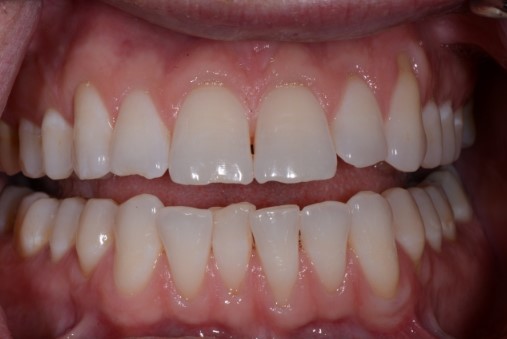

Incisal chipping

Have you ever had a patient ask you to “just smooth” a chip in one of their front teeth? If the patient doesn’t know how that chip got there (fork, chewing fingernails, fishing line), our suspicions should lead toward an imbalance of the system. Check their mandibular movements in all directions. Assess how level their incisal planes match up. Look for the sharp spot in the opposing arch that notched the tooth, as they often match up like a puzzle piece.

Tooth wear

Like pain, tooth wear can be multifactorial, but after a thorough history and clinical exam, we should be able to sort out tooth wear caused by extrinsic forces (acid erosion) vs. tooth wear caused by tooth-to-tooth contact (attrition).

Cases of attrition are often present in the unbalanced environment where a patient is naturally balancing themselves. The question here: What is the long-term consequence? Clinically, this can show anywhere from one canine with a flat incisal edge to an entire arch of teeth with completely flattened cusp tips. The worn area of one tooth or arch will have an equal and opposite pattern of wear in the other tooth or arch.

The idea is to look beyond a single tooth and appreciate the system of joints, muscles, and teeth. What impact, if any, does the imbalance have on the patient for the short term and the long term? How long will your dentistry last in the current environment?